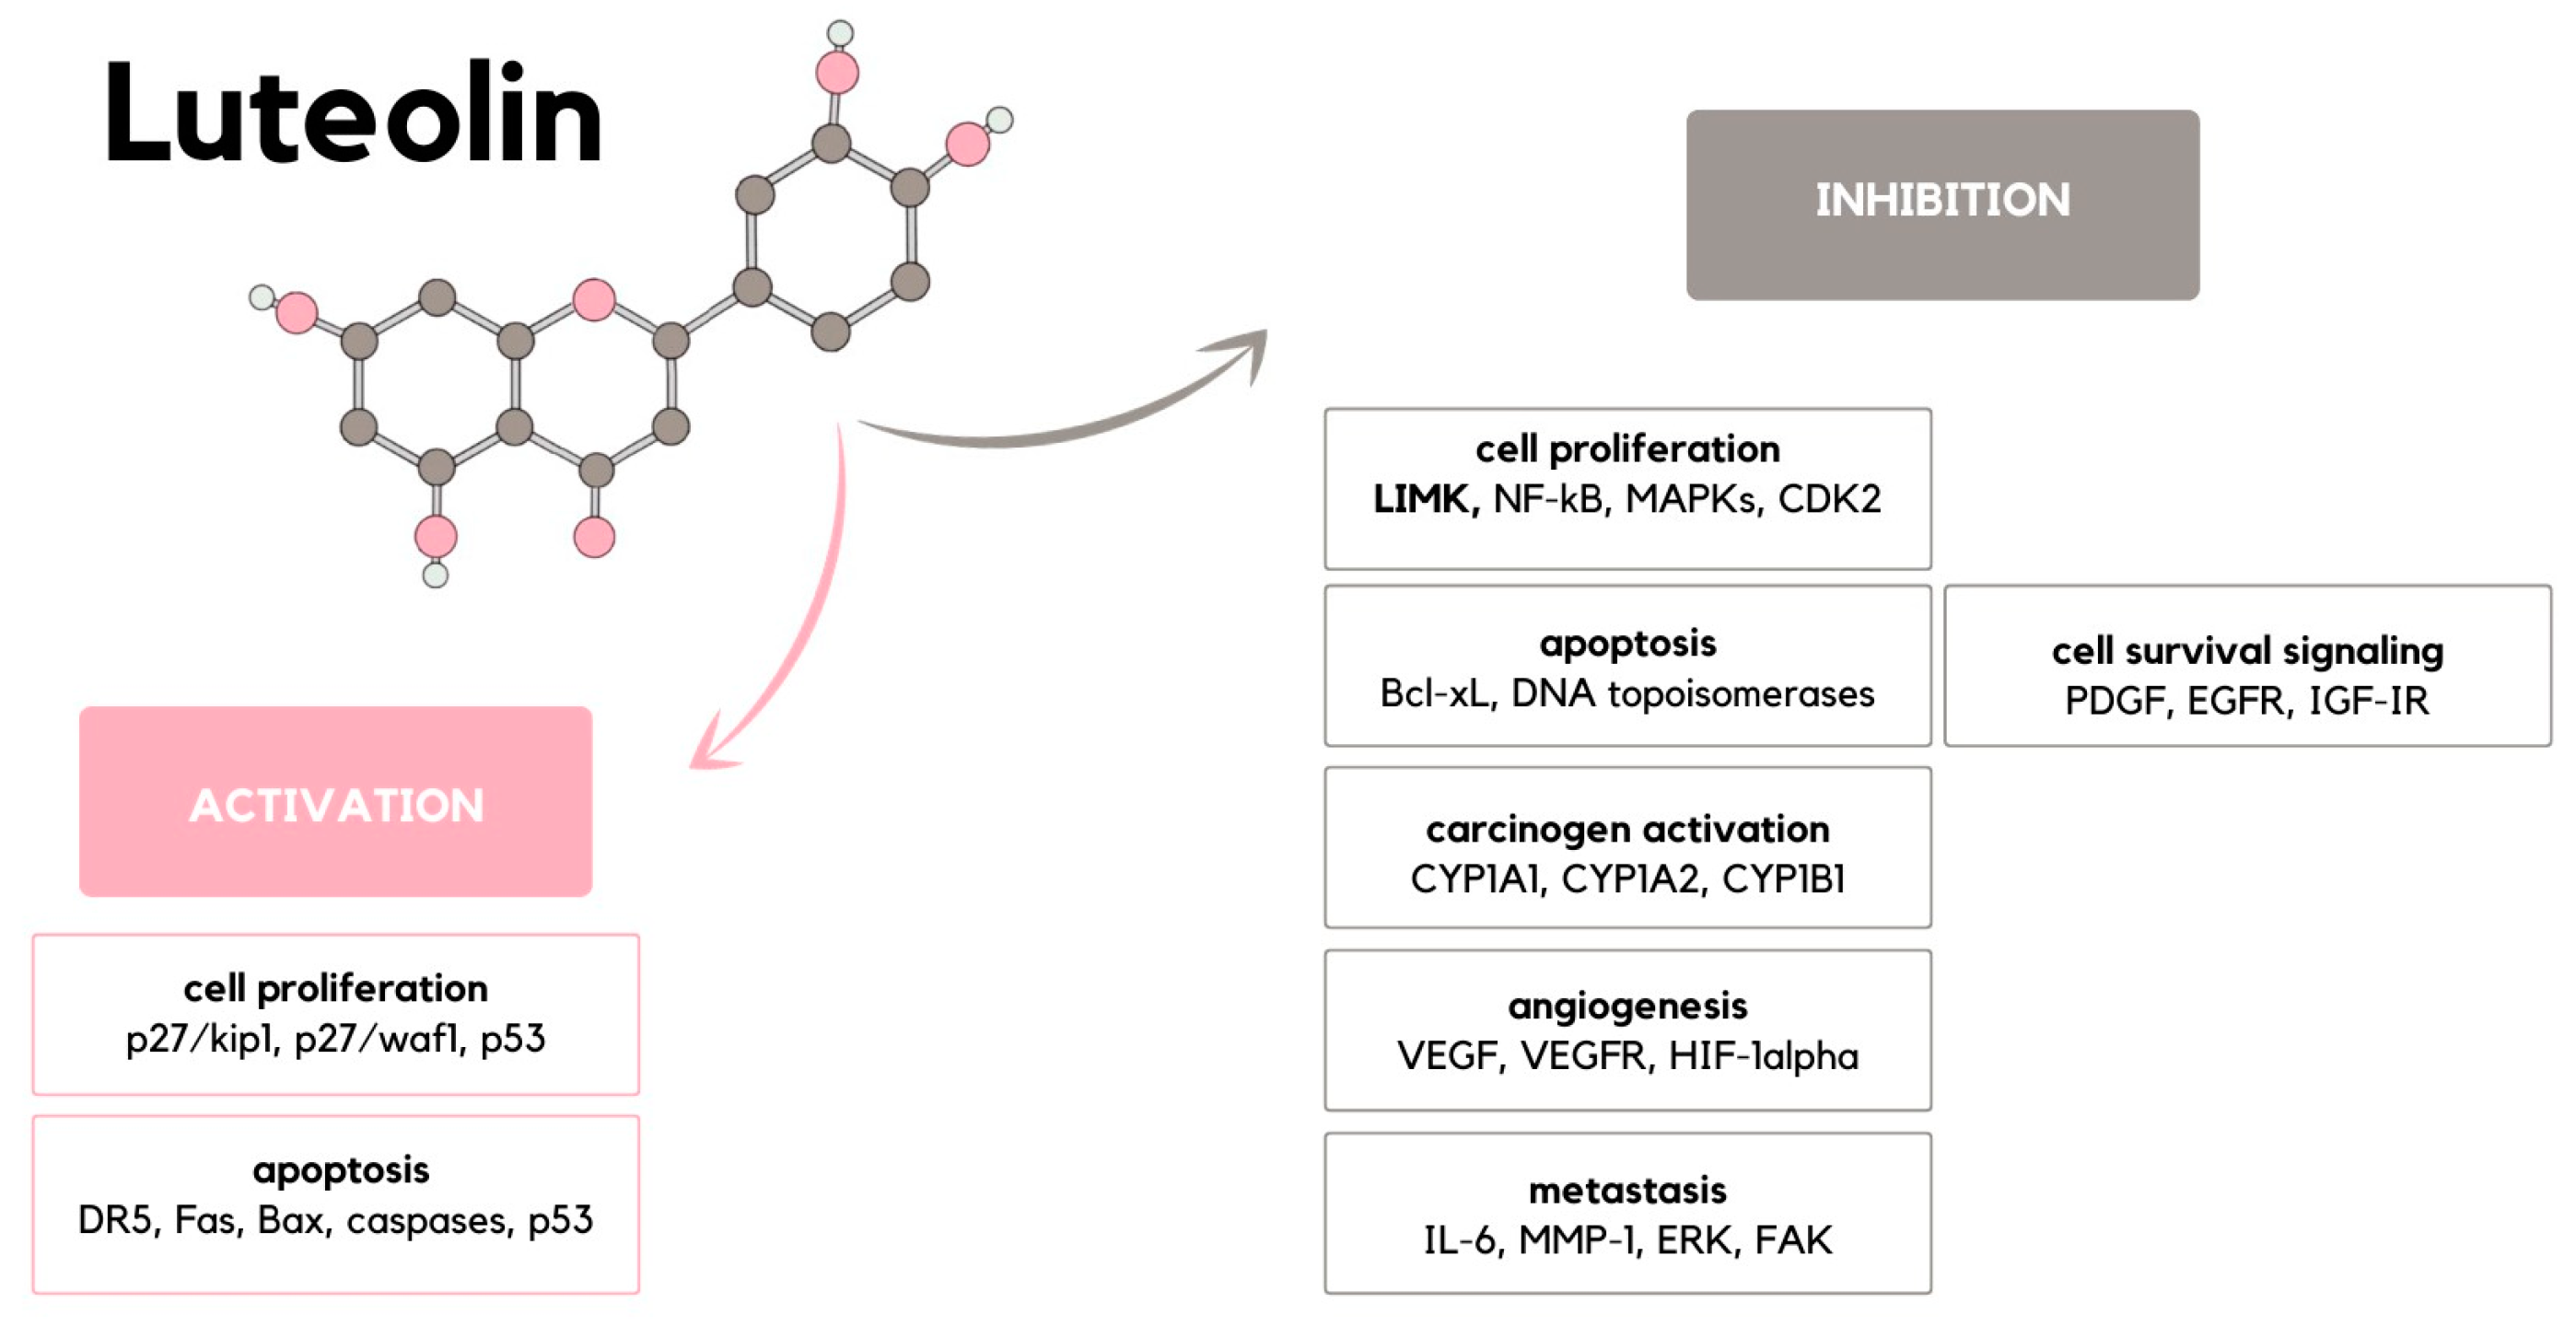

2. Carcinogenesis

3. Cell Proliferation

4. Apoptosis Induction

5. Carcinogen Activation

6. Angiogenesis

7. Metastasis